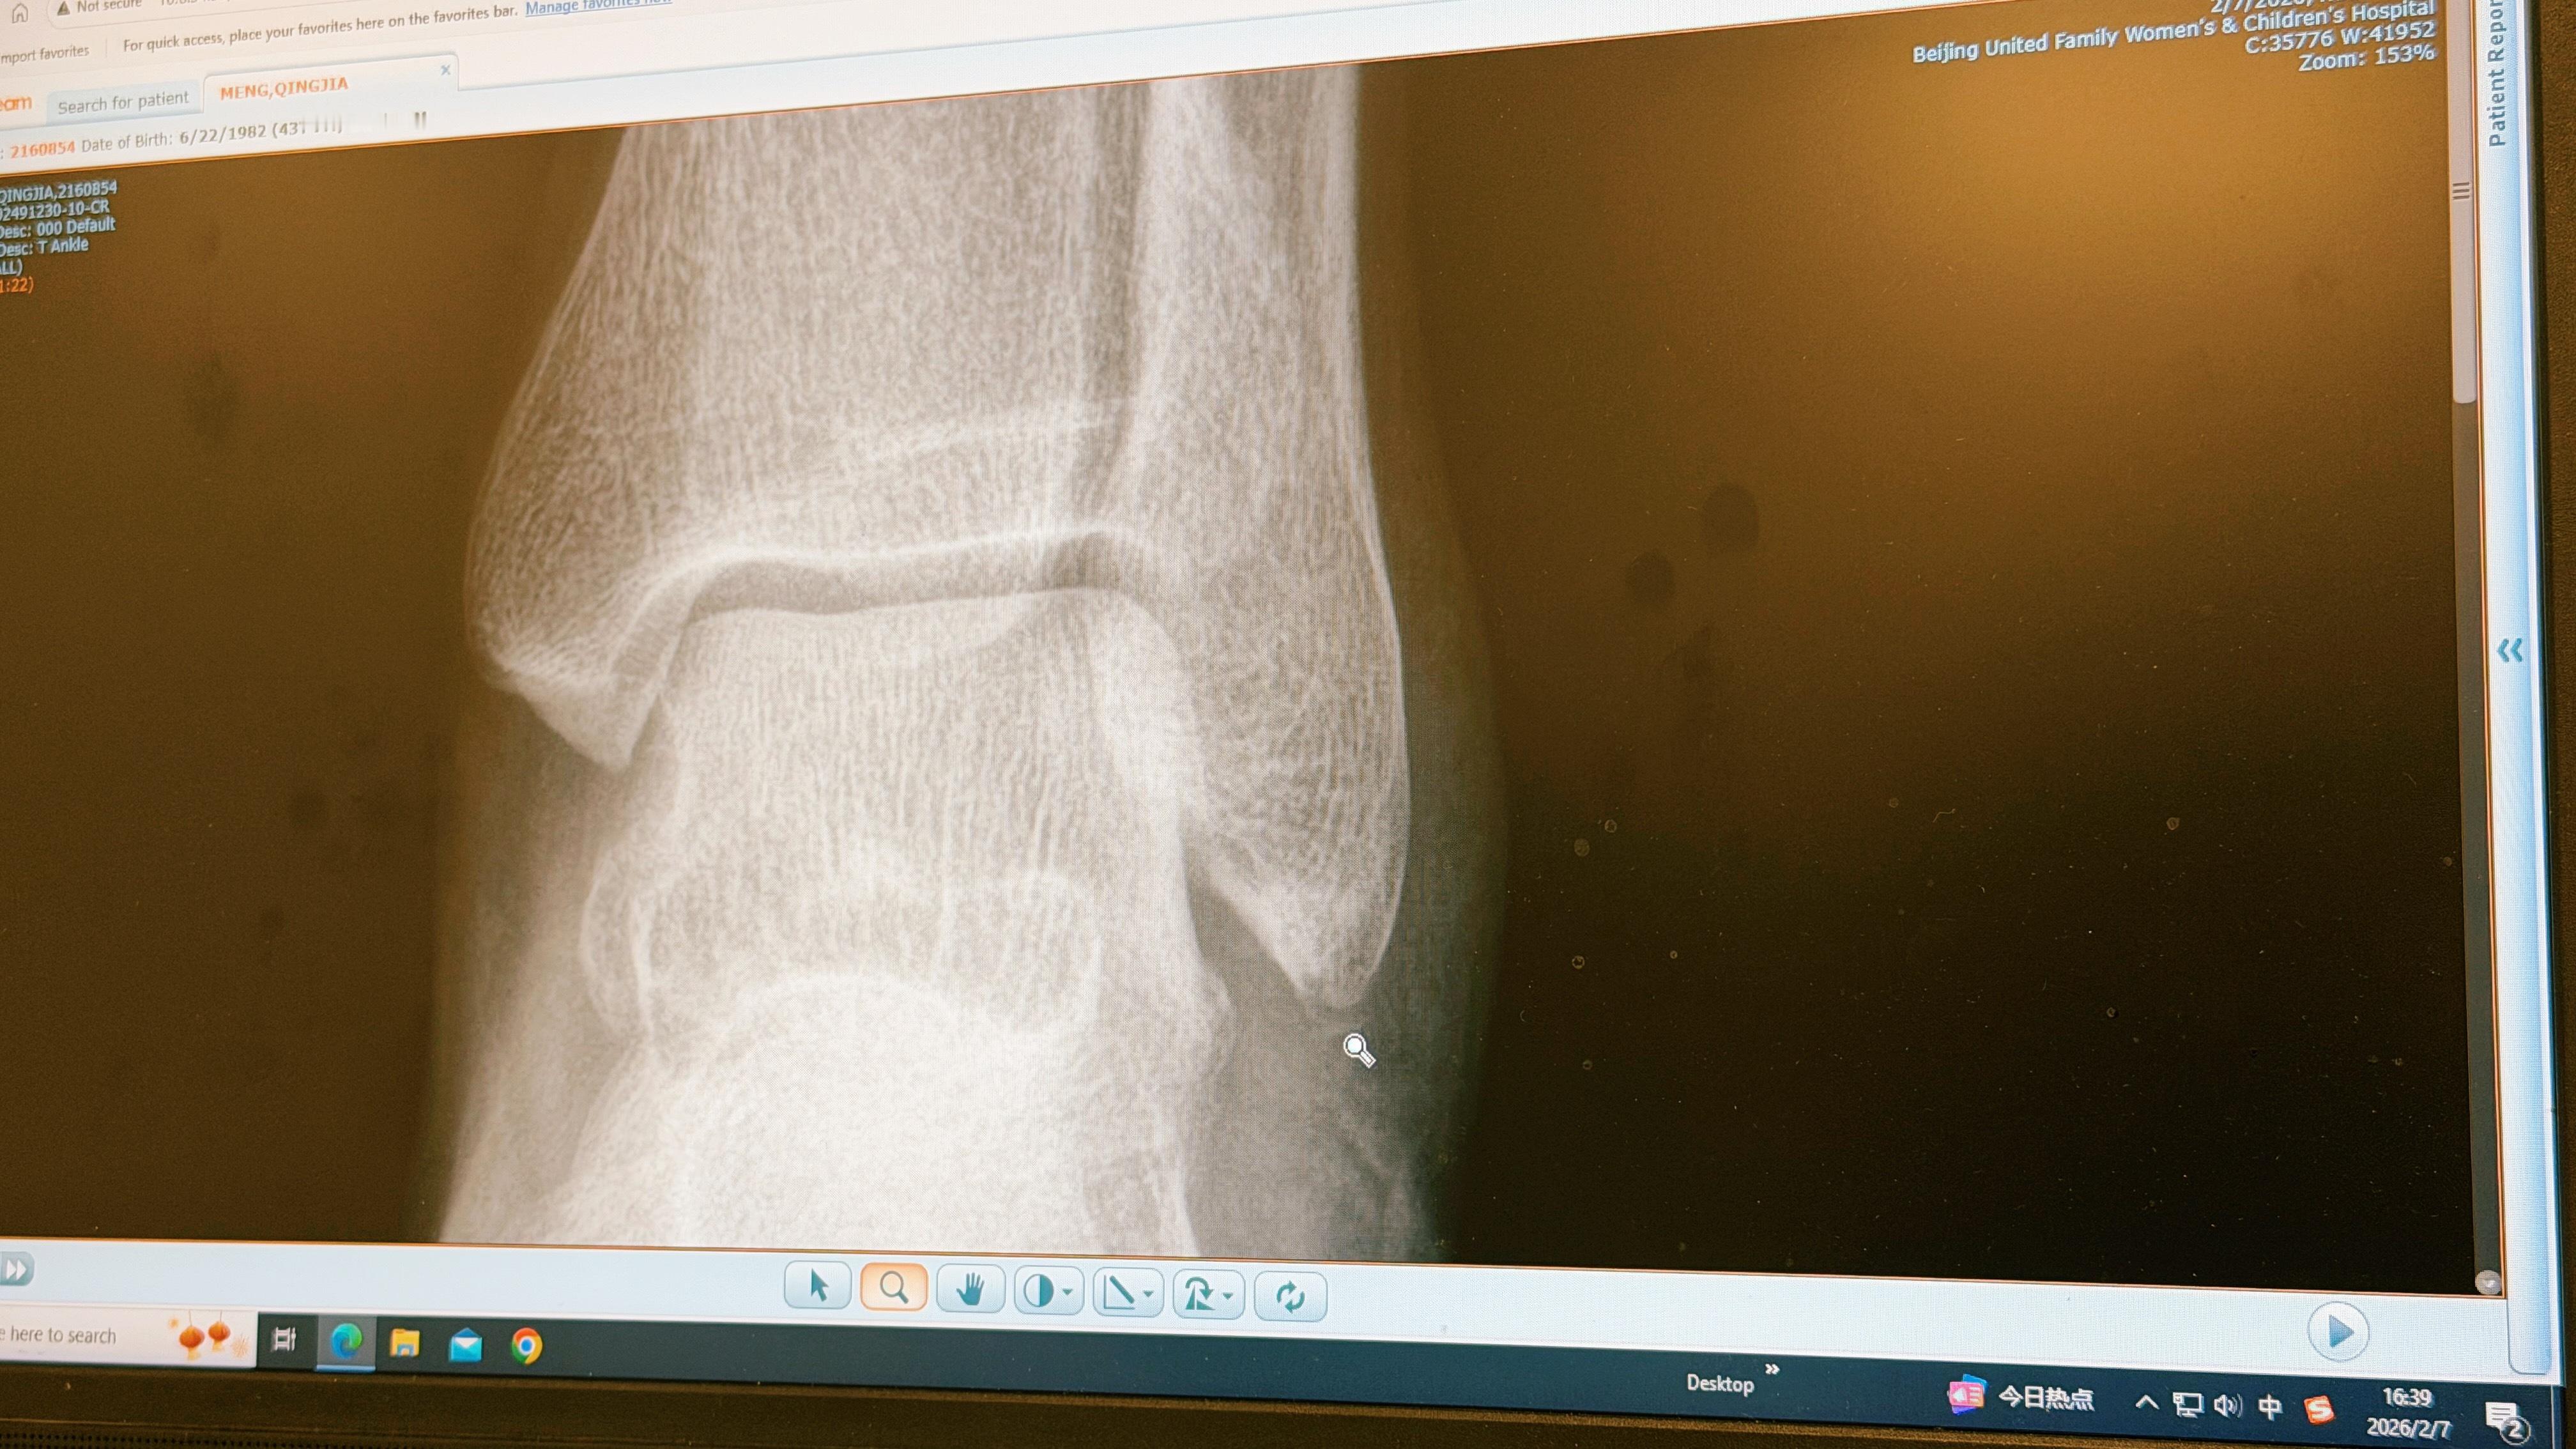

业余生涯最严重的一次“小伤”……撕脱性骨折…..意思是韧带没断,但把一小块骨头扯下来了